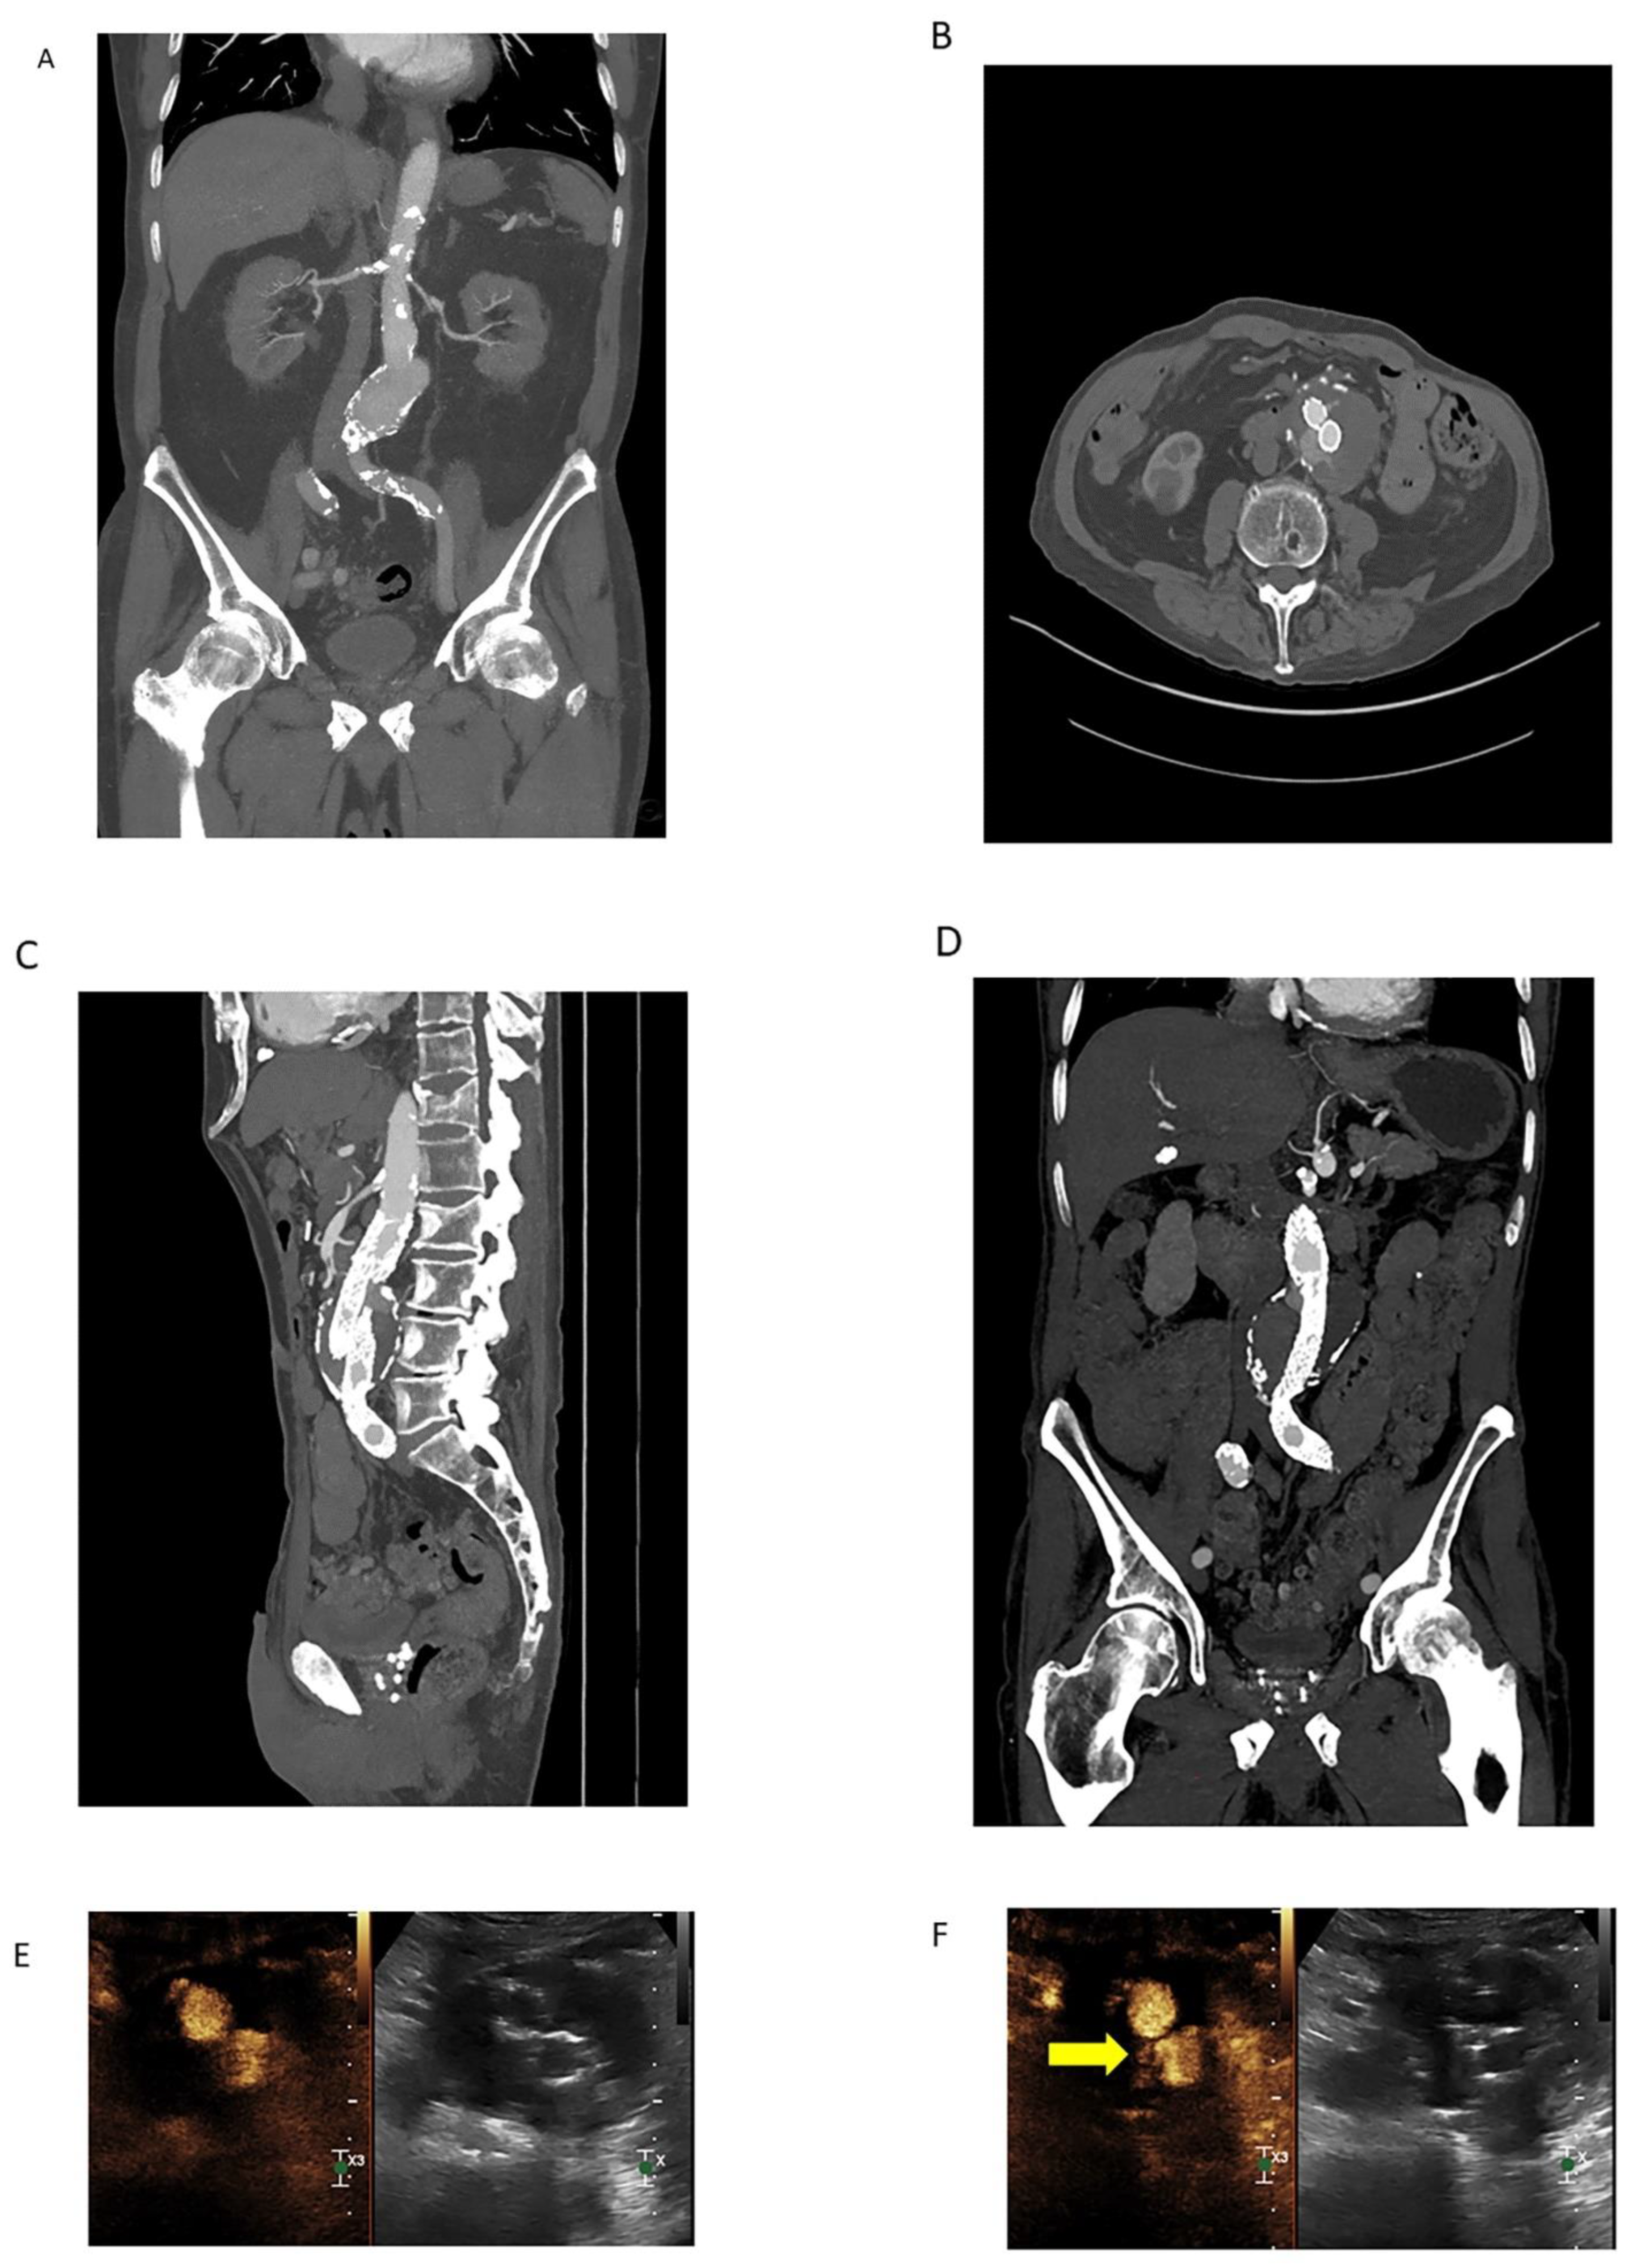

3.2.3. Contrast-Enhanced Ultrasound

- Bredahl, K.; Mestre, X.M.; Coll, R.V.; Ghulam, Q.M.; Sillesen, H.; Eiberg, J. Contrast-Enhanced Ultrasound in Vascular Surgery: Review and Update. Ann. Vasc. Surg. 2017, 45, 287–293. [Google Scholar] [CrossRef] [PubMed]

- Huang, D.Y.; Yusuf, G.T.; Daneshi, M.; Ramnarine, R.; Deganello, A.; Sellars, M.E.; Sidhu, P.S. Contrast-enhanced ultrasound (CEUS) in abdominal intervention. Abdom. Radiol. 2018, 43, 960–976. [Google Scholar] [CrossRef] [PubMed]

- Marschner, C.A.; Rübenthaler, J.; Froelich, M.F.; Schwarze, V.; Clevert, D.-A. Benefits of contrast-enhanced ultrasonography for interventional procedures. Ultrasonography 2021, 40, 207–216. [Google Scholar] [CrossRef] [PubMed]